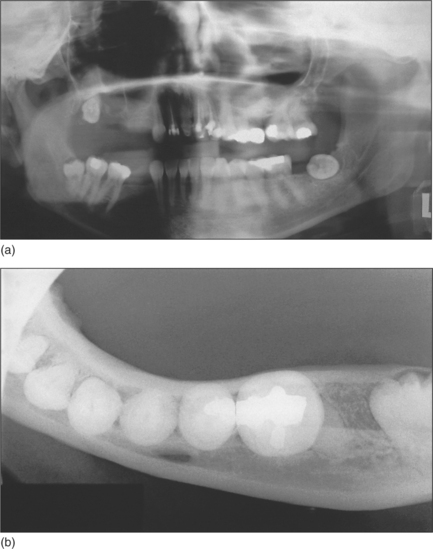

Page 53

Fig. 5.12 (a) Panoramic radiograph and (b) mandibular occlusal radiographs of a buccolingually inclined lower left third molar.